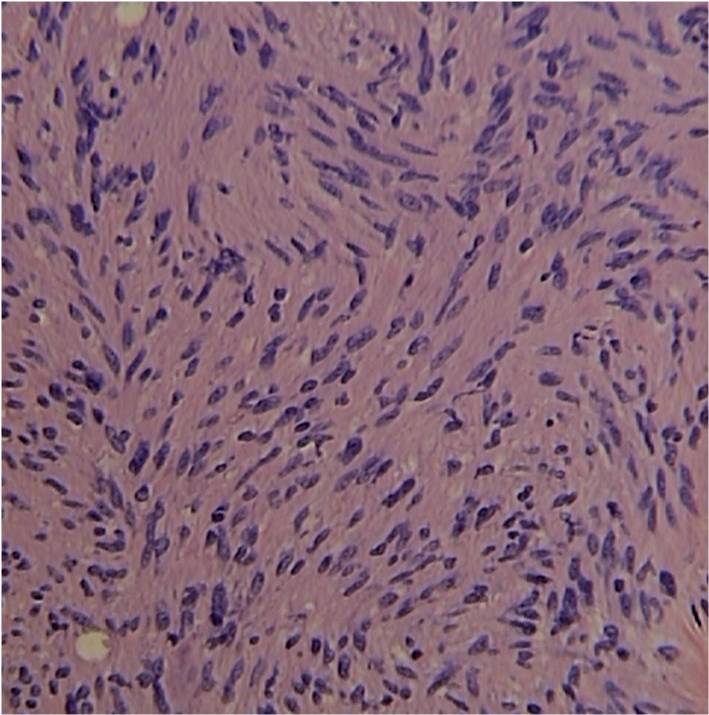

• Distinct Pattern of alternating Antoni A and B areas

o Antoni A Area: Cellular area arranged in short bundles or interlacing fascicles

Spindle cells with wavy appearing nuclei. (Fig. 5 & 6)

Fig. 5-7 Microscopic Pathology demonstrates 2 different patterns; Antoni A area with spindled hypercellular distribution with wavy appearing nuclei (Fig 5 & 6A) that palisades, known as Verocay Bodies (Fig 6B). Antoni B area is less cellular and more myxoid (Fig 7) than the Antoni A area. Mitotic activity is not visible.